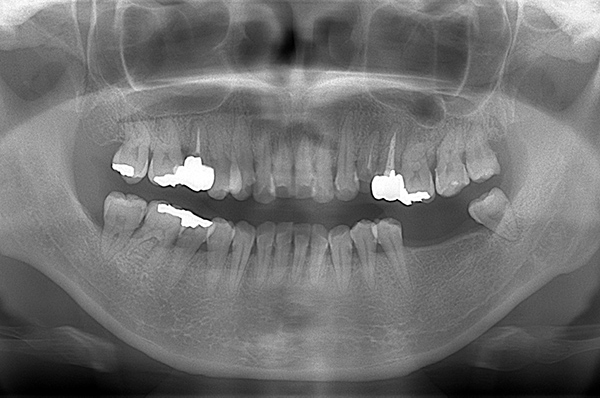

患者様の初診時レントゲン写真

【担当医師所見】

咬合平面の整頓の必要性 有

交叉咬合、オーバージェットの是正

左下奥歯は親知らずが原因でクラウン(かぶせ物)の下まで虫歯になっています。 またその手前の歯は根中央部に大きな透過像(黒い像)が見られます。クラウン除去後、マイクロスコープ下で確認したところ中央部は亀裂が入り保存不可能な状態になっており抜歯となりました。

また右上6番にも大きな透過像があり虫歯となっていることがわかります。

①親知らず手前の歯はクラウン(白い不透過像)直下に大きな透過像(黒い部分)が見られこのような場合は抜歯になる確率が高いです。

②歯根分岐部(中央部)に及ぶ歯周炎ー根尖性歯周炎の原因はクラウン除去後にマイクロスコープ下にて破折線を確認したため抜歯となりました。